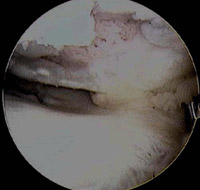

Arthroscopic picture of torn medial meniscus in chronically ACL-deficient knee. In this case, the torn meniscus is pushed forward [yellow star] and locked in front of the knee [called a "bucket handle" meniscus tear], so the patient could not straighten out the leg.